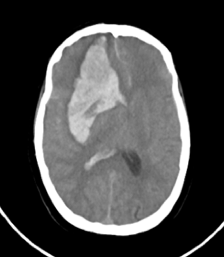

Ante la buena evolución, se decidió el traslado a una sala general. A las 24 h, el cuadro se complicó con un episodio súbito de depresión del sensorio, con un puntaje de la escala de Glasgow 8/15, pupilas mióticas e hiporreactivas. Por tal motivo, se decidió realizar una nueva tomografía computarizada de cráneo que reveló un hematoma intraparenquimatoso cerebral derecho (Figura 1). Volvió a ingresar en la Unidad de Cuidados Intensivos, recibió asistencia respiratoria mecánica y fue sometida a cirugía mediante una evacuación del hematoma intracerebral derecho, craniectomía descompresiva frontotemporal derecha y plástica dural (Figura 2). A los siete días del procedimiento quirúrgico, tuvo registros febriles, por lo cual se decidió realizar dos hemocultivos, retrohemocultivos, un aspirado traqueal y una punción lumbar, cuyo resultado fue: líquido cefalorraquídeo turbio con 10.000 elementos (80% polimorfonucleares, 20% monomorfonucleares), proteínas 0,6 g, glucosa 0,20 g y lactato 20 mmol/l. Se administró un tratamiento empírico con meropenem/vancomicina. A las 48 h, los resultados del estudio bacteriológico informaron Enterococcus faecalis en el cultivo de líquido cefalorraquídeo y hemocultivos X2 con la misma sensibilidad y resistencia. Se procedió a ajustar el tratamiento antibiótico según el antibiograma, por lo que se suspendió la combinación de meropenem/vancomicina y se administró ampicilina sulbactam/ceftriaxona. A las 72 h, la paciente sufre un paro cardiorrespiratorio y fallece.

Figura 1. Hematoma intraparenquimatoso

cerebral derecho.